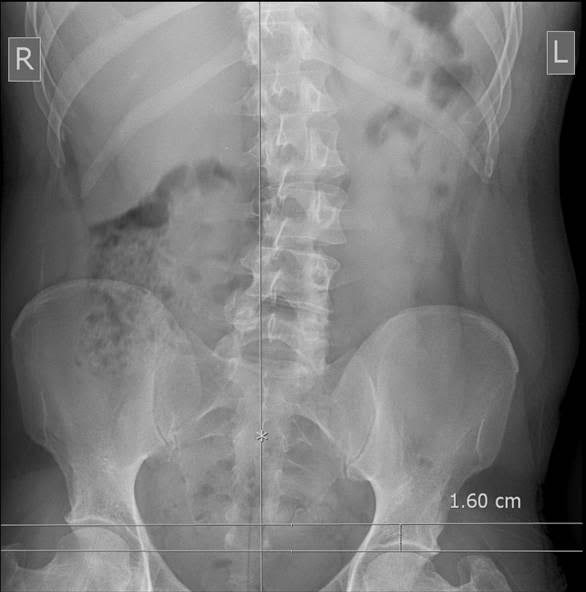

What Is Functional Short Leg Syndrome . The functional short leg is different from the structural short leg. It is a unilateral asymmetry of the lower extremity without any shortening of the osseous components of the lower limb. Often, the right leg is the functionally short leg. Flld may be caused by. Sometimes athletes who run on hard surfaces develop foot problems that lead to functional sls. Most cases of unequal leg length are congenital conditions (those people are born with). What causes one leg to be longer than the other? When someone has anatomic sls, the bones of the legs are literally two different lengths. On the other hand, if the legs appear to have different lengths but structurally are intact, this is functional sls. In functional short legs, the patient is often accompanied by back pain on the right or left side of the sacroiliac joint. This can be caused by muscular, ligamentous, or other soft tissue injuries,. This condition can affect both children and adults. Functional sls is where one leg becomes shorter due to the mechanics of the lower body. When someone has functional sls, the. Some examples include conditions where the foot turns outward, or the pelvis is misaligned.